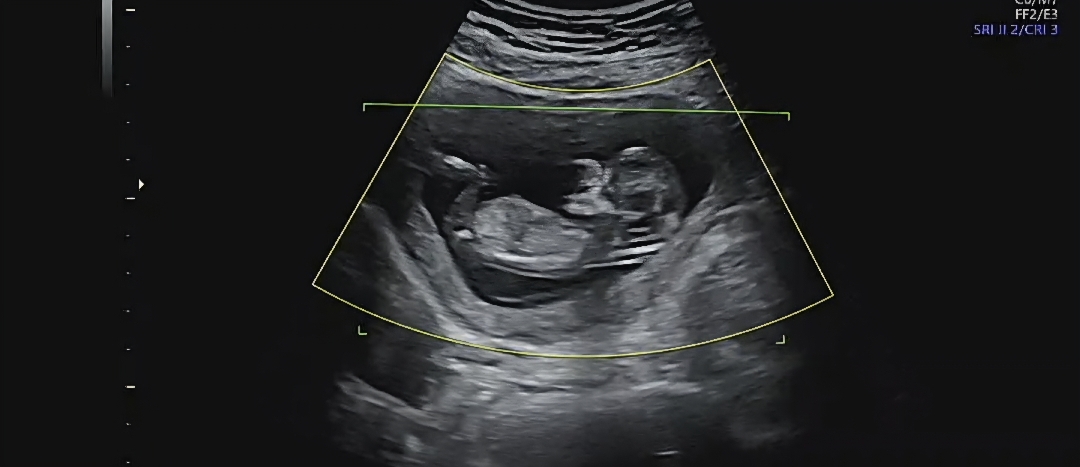

12주 2일차에 찍은 사진인데 선배님들이 보시기엔 딸일까요 아들일까용🤭🤭